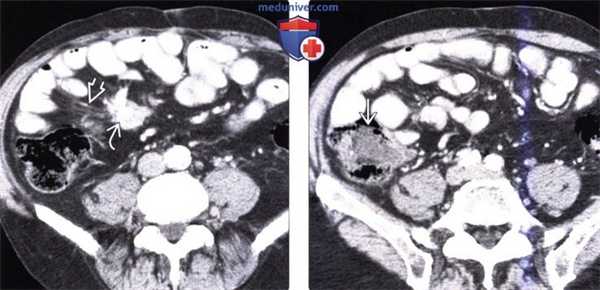

Нейроэндокринная опухоль двенадцатиперстной кишки у женщины 64 лет, степень злокачественности G1 (карциноид).

(а) При эндоскопии в двенадцатиперстной кишке выявляется субэпителиальная опухоль с гладкой поверхностью (стрелки). Отмечается интактность слизистой, покрывающей опухоль.

(б) При рентгенографии с бариевым контрастированием во втором отделе двенадцатиперстной кишки визуализируется субэпителиальная опухоль (стрелка) с ровными четко очерченными границами. Было установлено, что опухоль представляет собой карциноид. Нейроэндокринный рак тощей кишки с метастазированием в лимфатические узлы.

(а) При КТ с контрастированием визуализируется эксцентрическое утолщение стенки (стрелки) тощей кишки, которая спаяна с увеличенными брыжеечными лимфатическими узлами (звездочка). Множественное поражение лимфатических узлов метастазами отмечается в парааортальной области (указатели).

(б) При ПЭТ-КТ с использованием 18F-FDG выявляется гиперметаболическое поражение, вовлекающее тощую кишку и прилежащую часть брыжейки (стрелки). В пораженных метастазами лимфатических узлах парааортальной области также отмечается усиленный метаболизм.